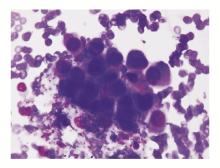

癌细胞骨髓转移(未分类):癌细胞常成团出现于片尾和边缘。细胞体积大,大小不一,呈现癌细胞特有的一“大”(细胞体积大,核大,核仁大而明显),二“黑”(核染色质增粗深染)、三“挤”(排列极性紊乱)、四“不规则”(大小不一,畸形)等特点,由于形态、排列不典型,故难以鉴别类型,见 图1。